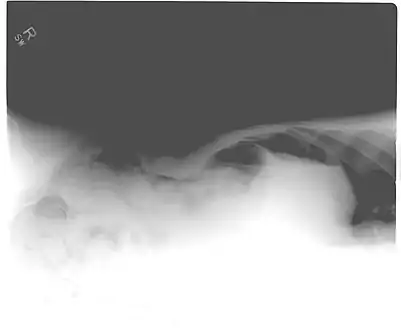

When present, pneumoperitoneum can often be seen on projectional radiography, but small amounts are often missed, and CT scan is nowadays regarded as a criterion standard in the assessment of a pneumoperitoneum.[26] CT can visualize quantities as small as 5 cm³ of air or gas.

Signs that can be seen on projectional radiography are shown below:

The Cupola sign is seen when air is accumulated under the central tendon of the diaphragm.[31]